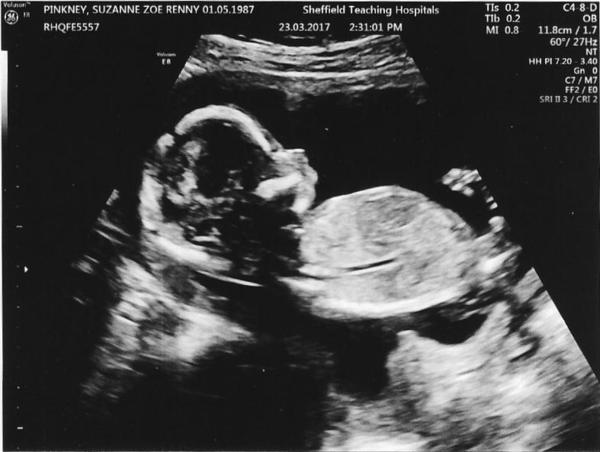

Well, if we're going to post scan photos I'll post mine from yesterday! My son appears to be going for swimming medals, the consultant kept having to retake the stills to get the measurements because he was moving so much, started doing backstroke at one point and playing with his umbilical cord... practising already for the teenage years perhaps! I had an extra scan at 16 weeks because of the high NT measurement but everything looks absolutely fine, saw most of his internal organs, brain, face, and even got to see the four chambers of his heart beating as well as hearing it which was amazing.

oliversmummy26 · 27/03/2017 10:28

As it was Mother's Day they let us have a free 4D colour photo Smile

Olivers gorgeous scan pic!

Lovely pic olivers